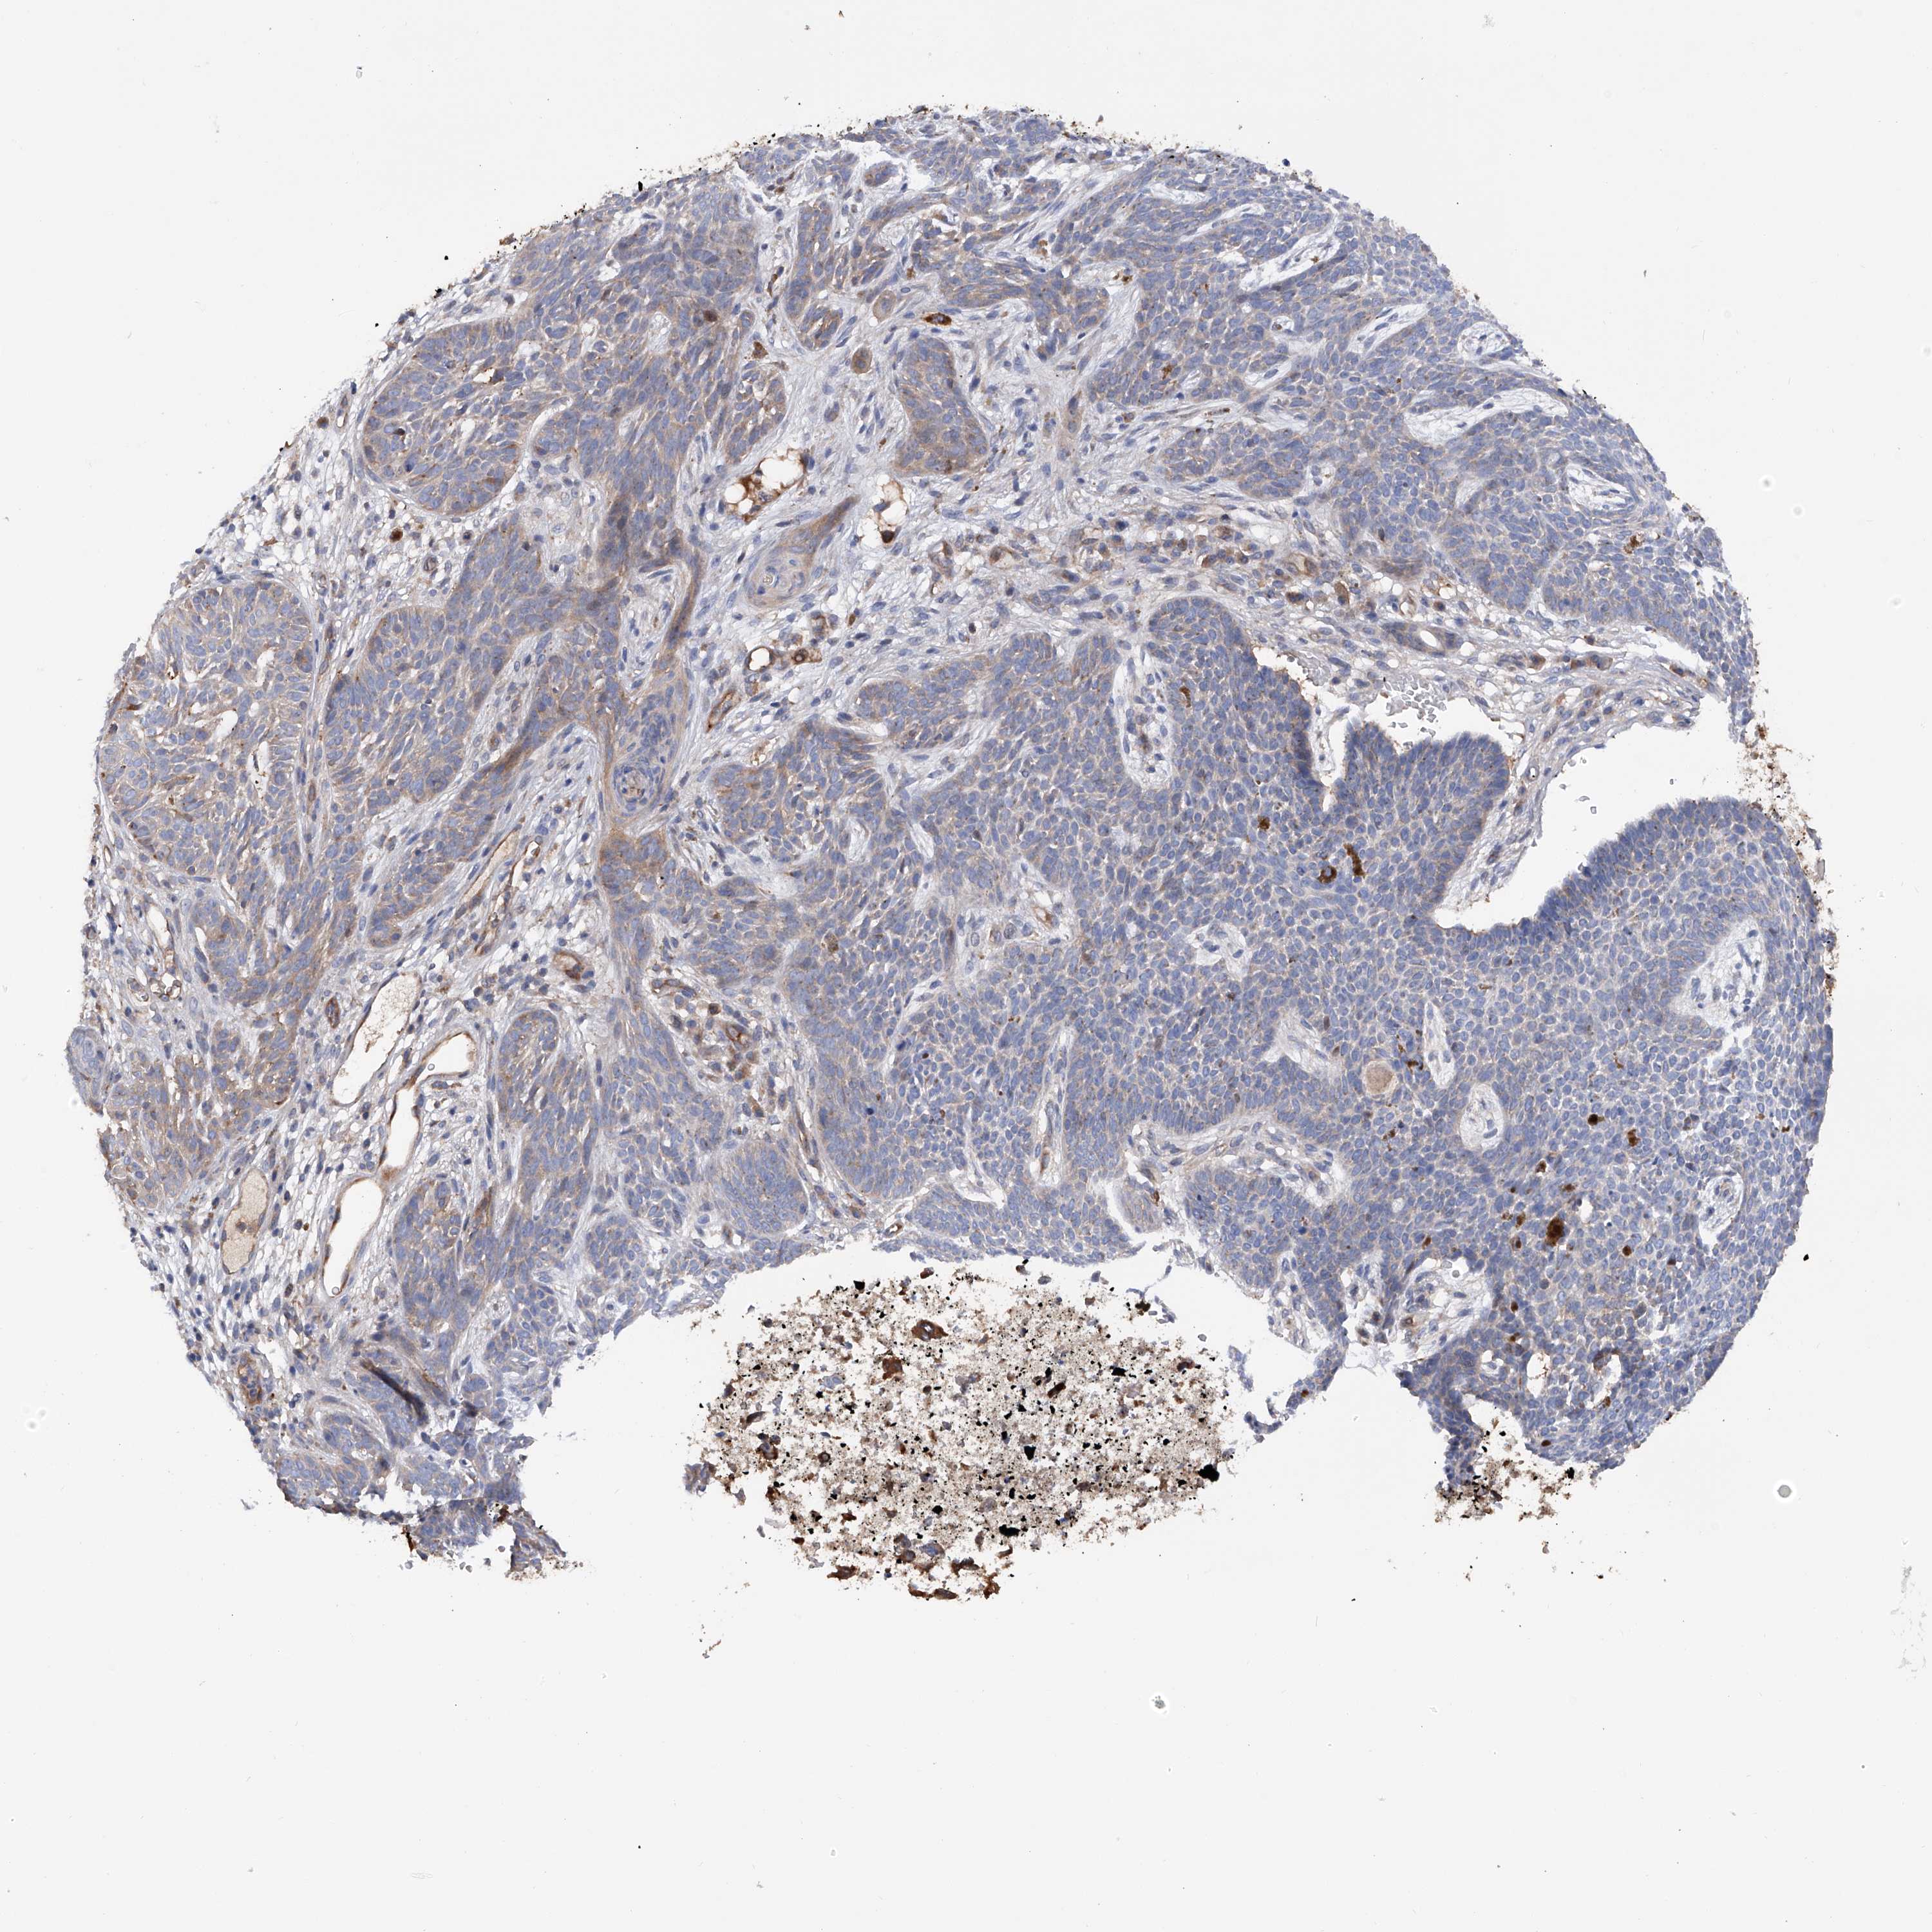

Basal cell and squamous cell cancer

SKIN CANCER - Protein expressioni

A mouse-over function shows sample information and annotation data. Click on an image to view it in a full screen mode. Samples can be filtered based on level of antibody staining by selecting one or several of the following categories: high, medium, low and not detected. The assay and annotation is described here.

Each image is clickable and will lead to virtual microscopy that enables deeper exploration of all samples and also displays staining intensity scores, fraction scores and subcellular localization as well as patient and tissue information for each sample.

Antibody HPA030145

Staining

Not detected

Negative

None

Location

Squamous cell carcinoma, NOS